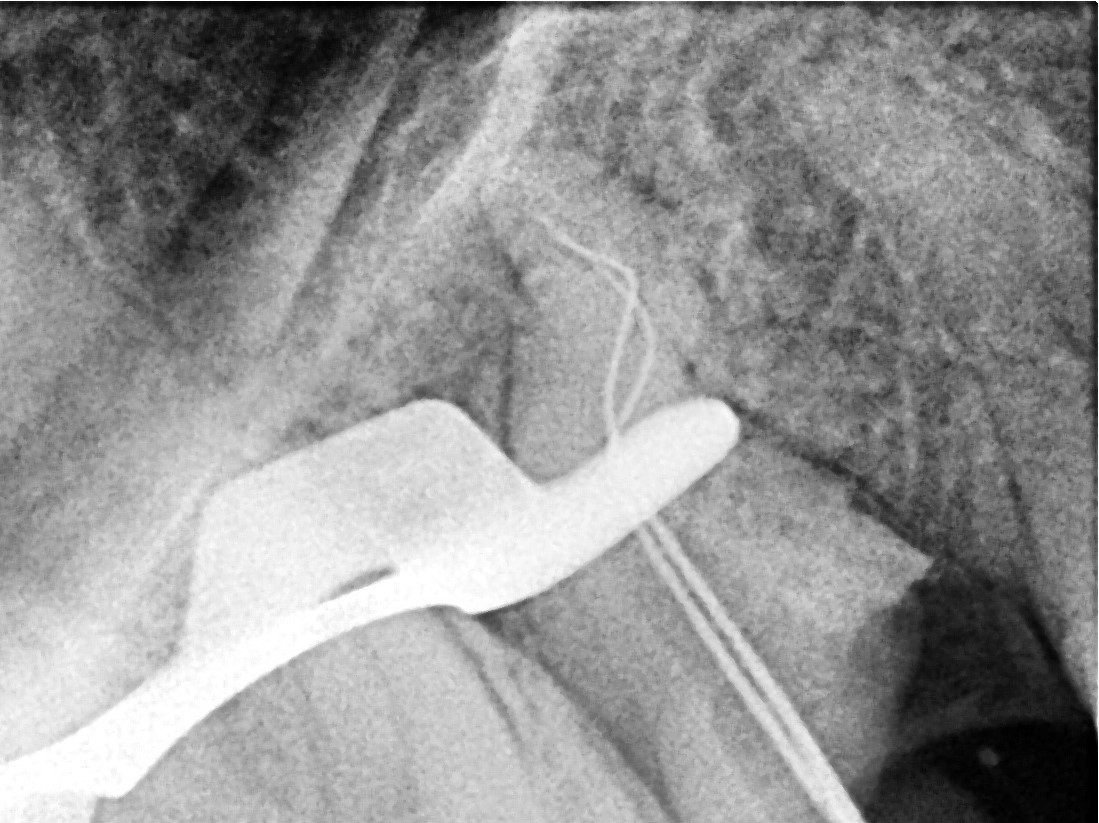

• After rubber dam isolation, treatment was initiated.

The coronal gutta-percha was removed using the SuperSystem “Retreat One” (25/06) file and the Perfect Micro H-shaper (image 2)